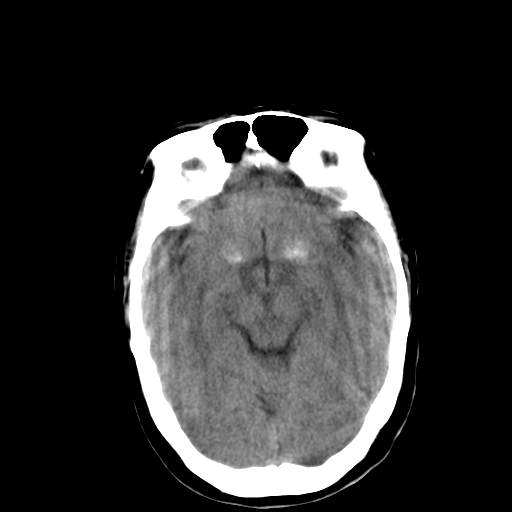

标题: CT13482:对称钙化!外伤就诊! [打印本页]

标题: CT13482:对称钙化!外伤就诊!

女,58 ,对称钙化!外伤就诊!